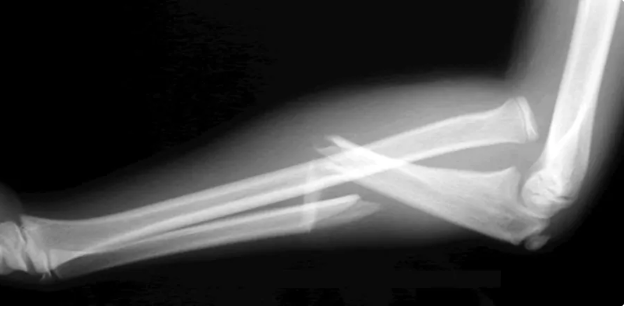

DX

Luxación de radio humeral y fx de diafisis del cúbito = Monteggia